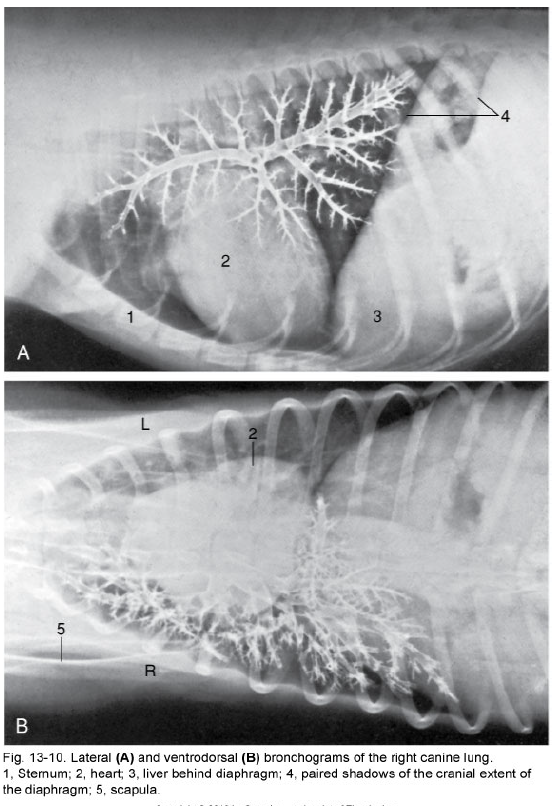

what are the structures shown in the bronchgram

what is the pathway of air from the trachea to lungs

trachea –> left and right primary bronchus (+ tracheal bronchus)